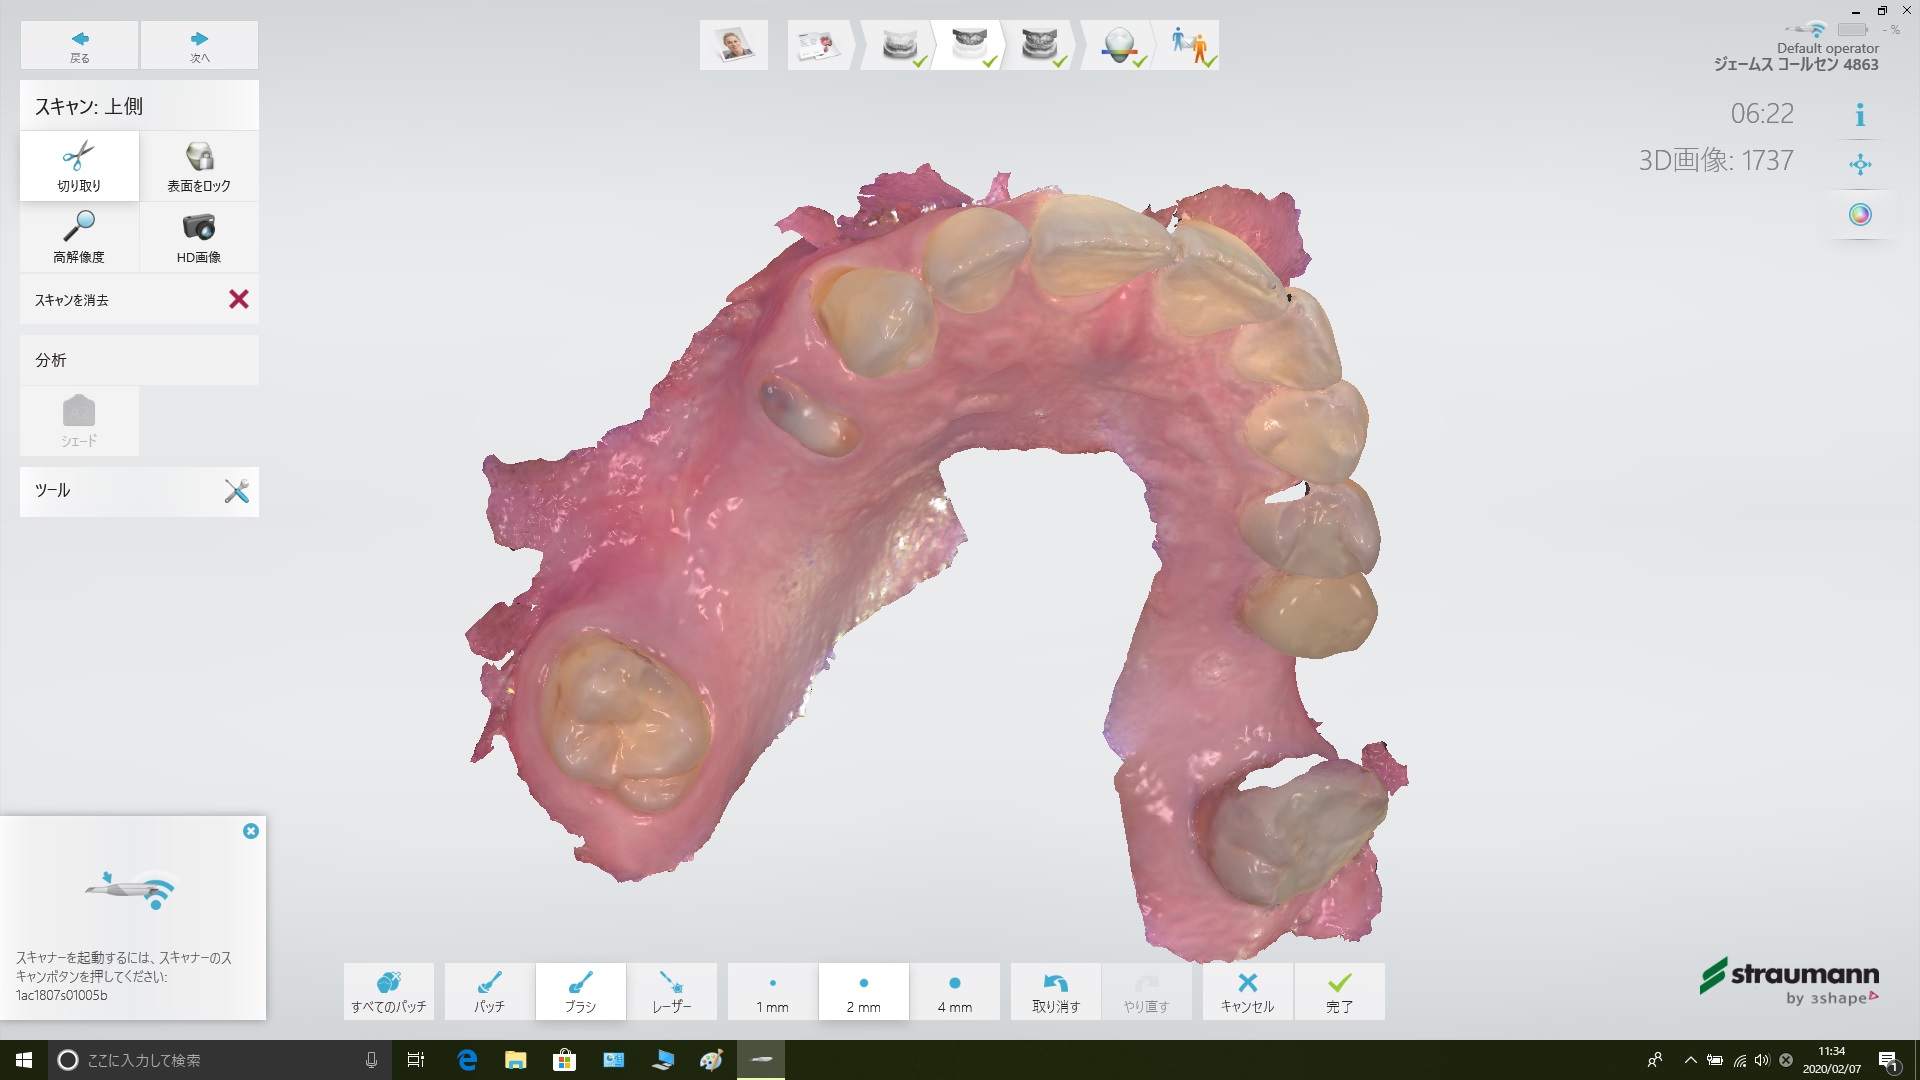

これも当院では口腔内スキャナーでスキャンしたデータを取り込むことで、とても適合良好で、通院回数も1回で作製が可能になりました。

グレーの模型は、口腔内スキャナーで取り込んだデータから作製した3Dプリンターに取り付けた「ノンクラスプデンチャー」です。